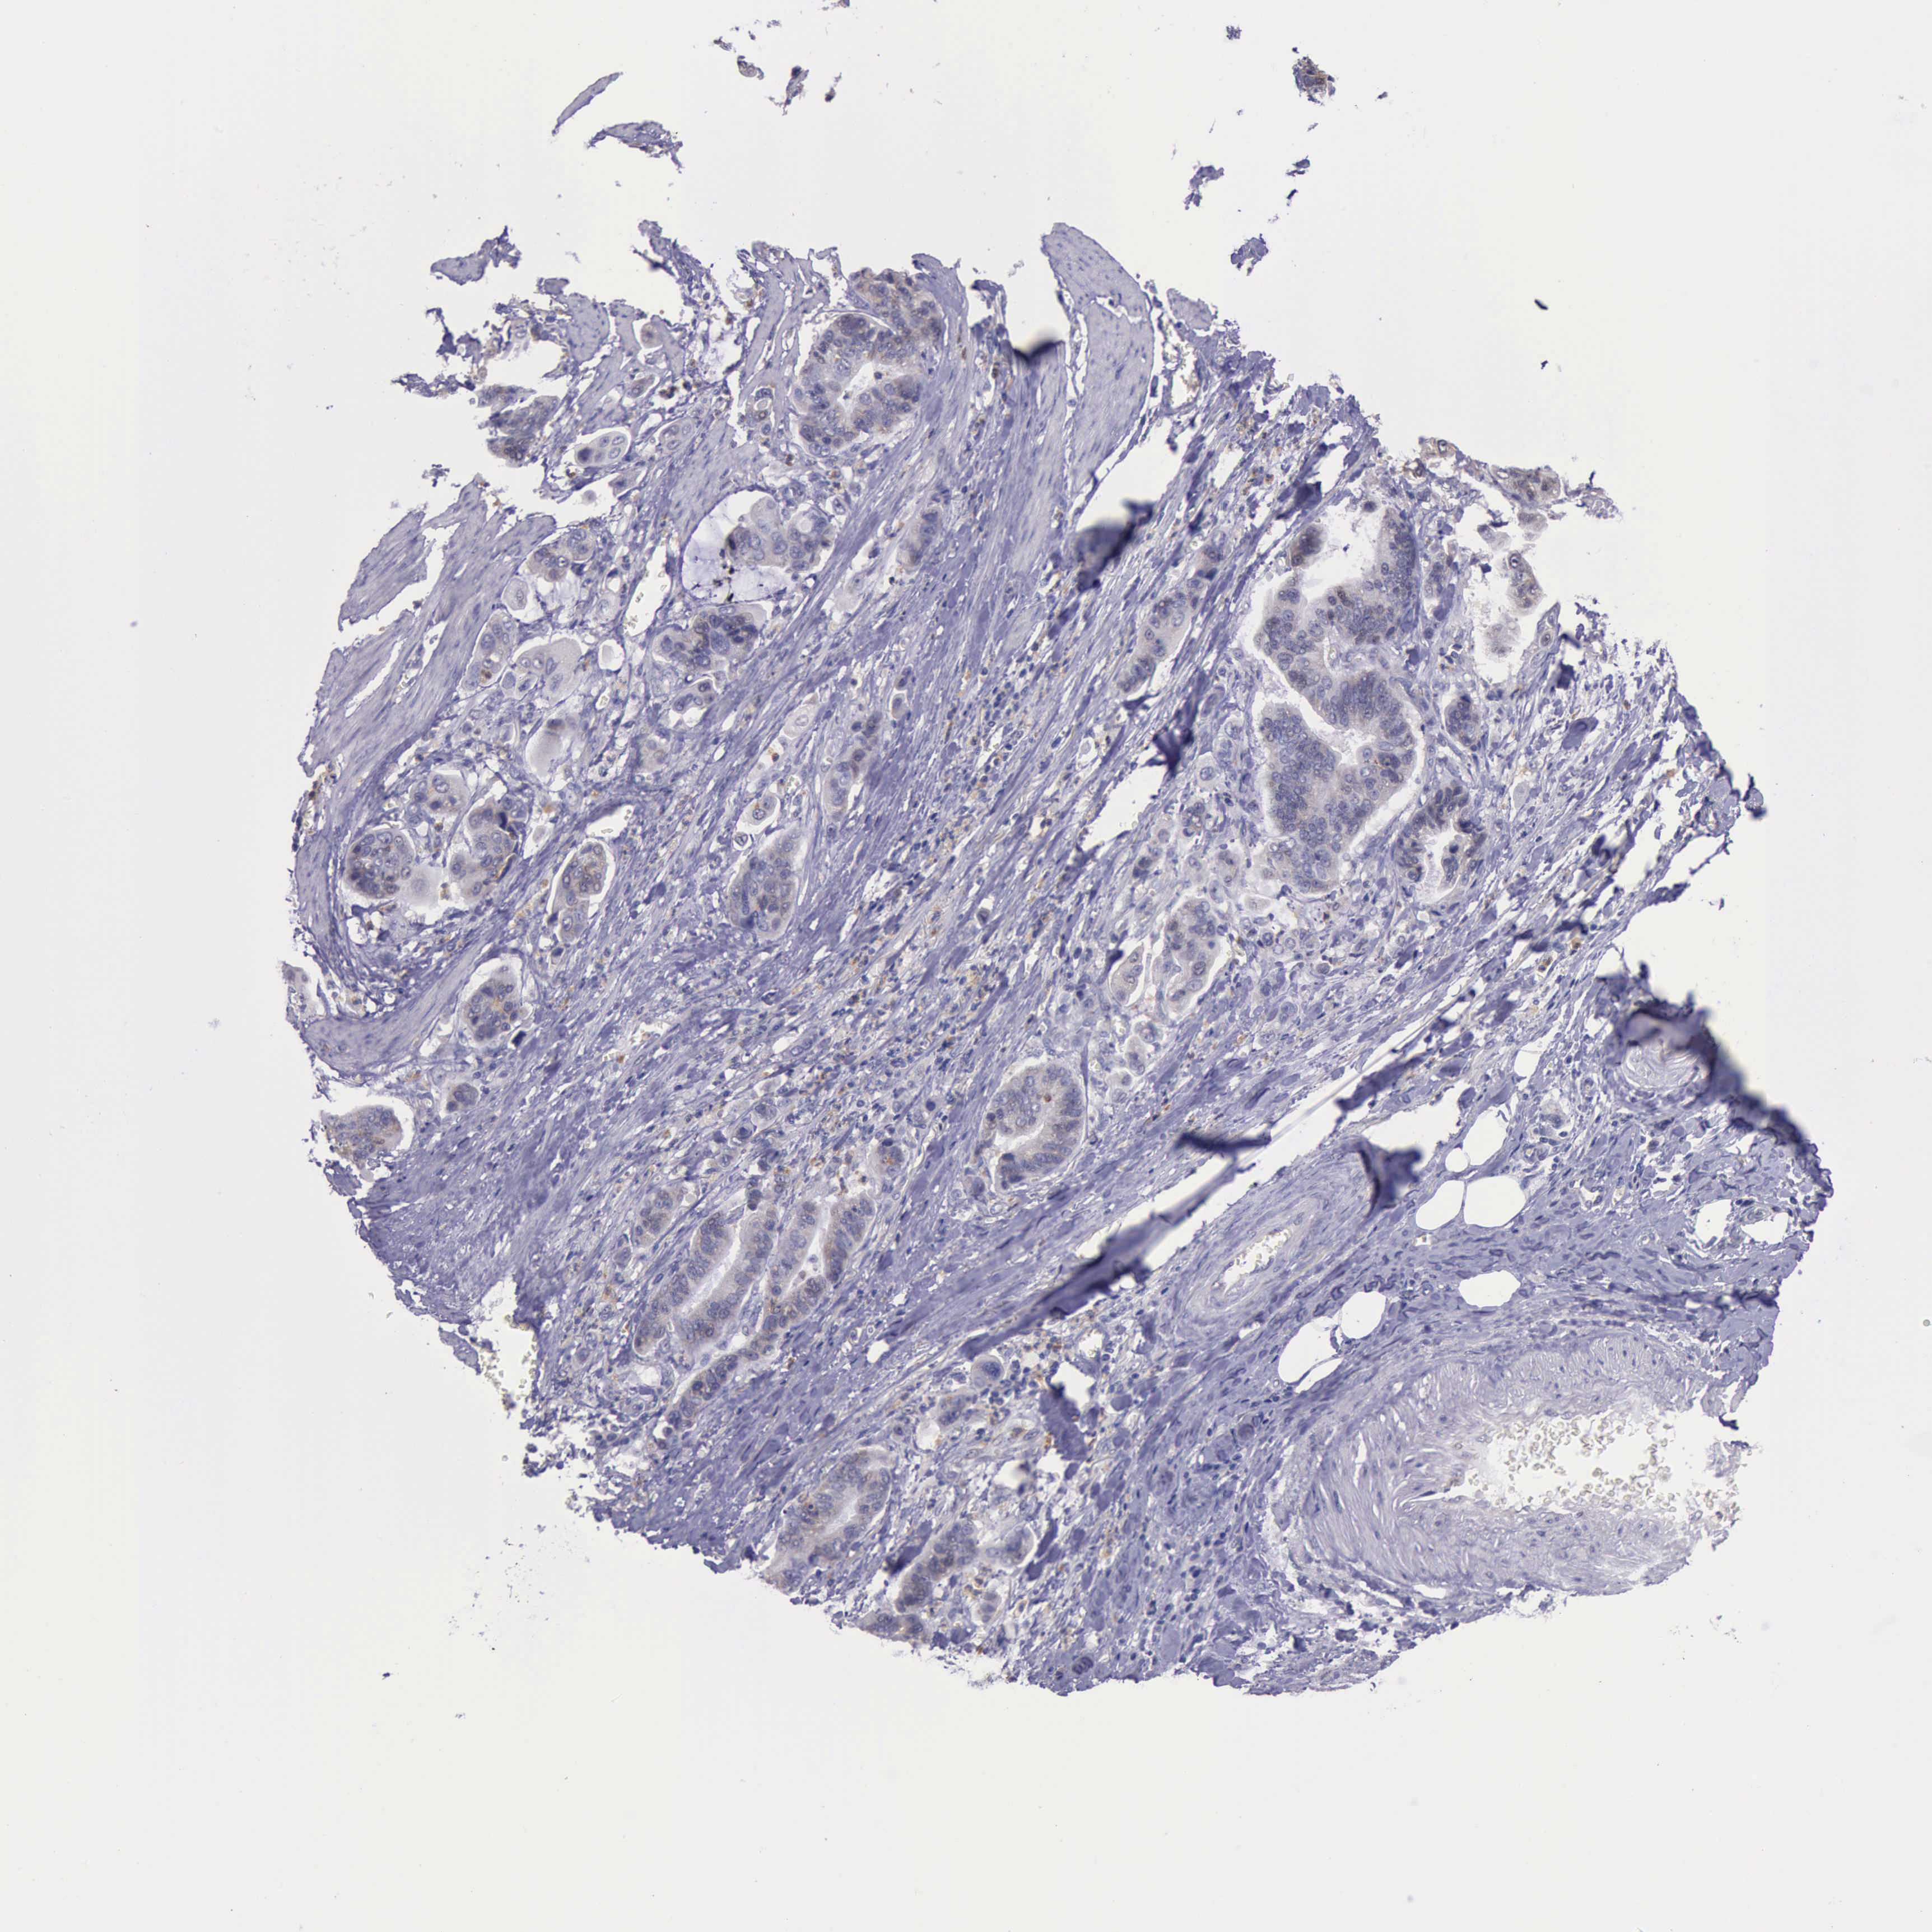

STOMACH CANCER - Protein expressioni

A mouse-over function shows sample information and annotation data. Click on an image to view it in a full screen mode. Samples can be filtered based on level of antibody staining by selecting one or several of the following categories: high, medium, low and not detected. The assay and annotation is described here.

Note that samples used for immunohistochemistry by the Human Protein Atlas do not correspond to samples in the TCGA dataset.

Antibody stainingi

Antibody staining in the annotated cell types in the current human tissue is reported as not detected, low, medium, or high, based on conventional immunohistochemistry profiling in selected tissues. This score is based on the combination of the staining intensity and fraction of stained cells.

Each image is clickable and will lead to virtual microscopy that enables deeper exploration of all samples and also displays staining intensity scores, fraction scores and subcellular localization as well as patient and tissue information for each sample.

Antibody HPA001208

Staining

High

Medium

Low

Not detected

Intensity

Strong

Moderate

Weak

Negative

Quantity

>75%

75%-25%

<25%

None

Location

Nuclear

Cytoplasmic/membranous

Cytoplasmic/membranous,nuclear

Adenocarcinoma, NOS